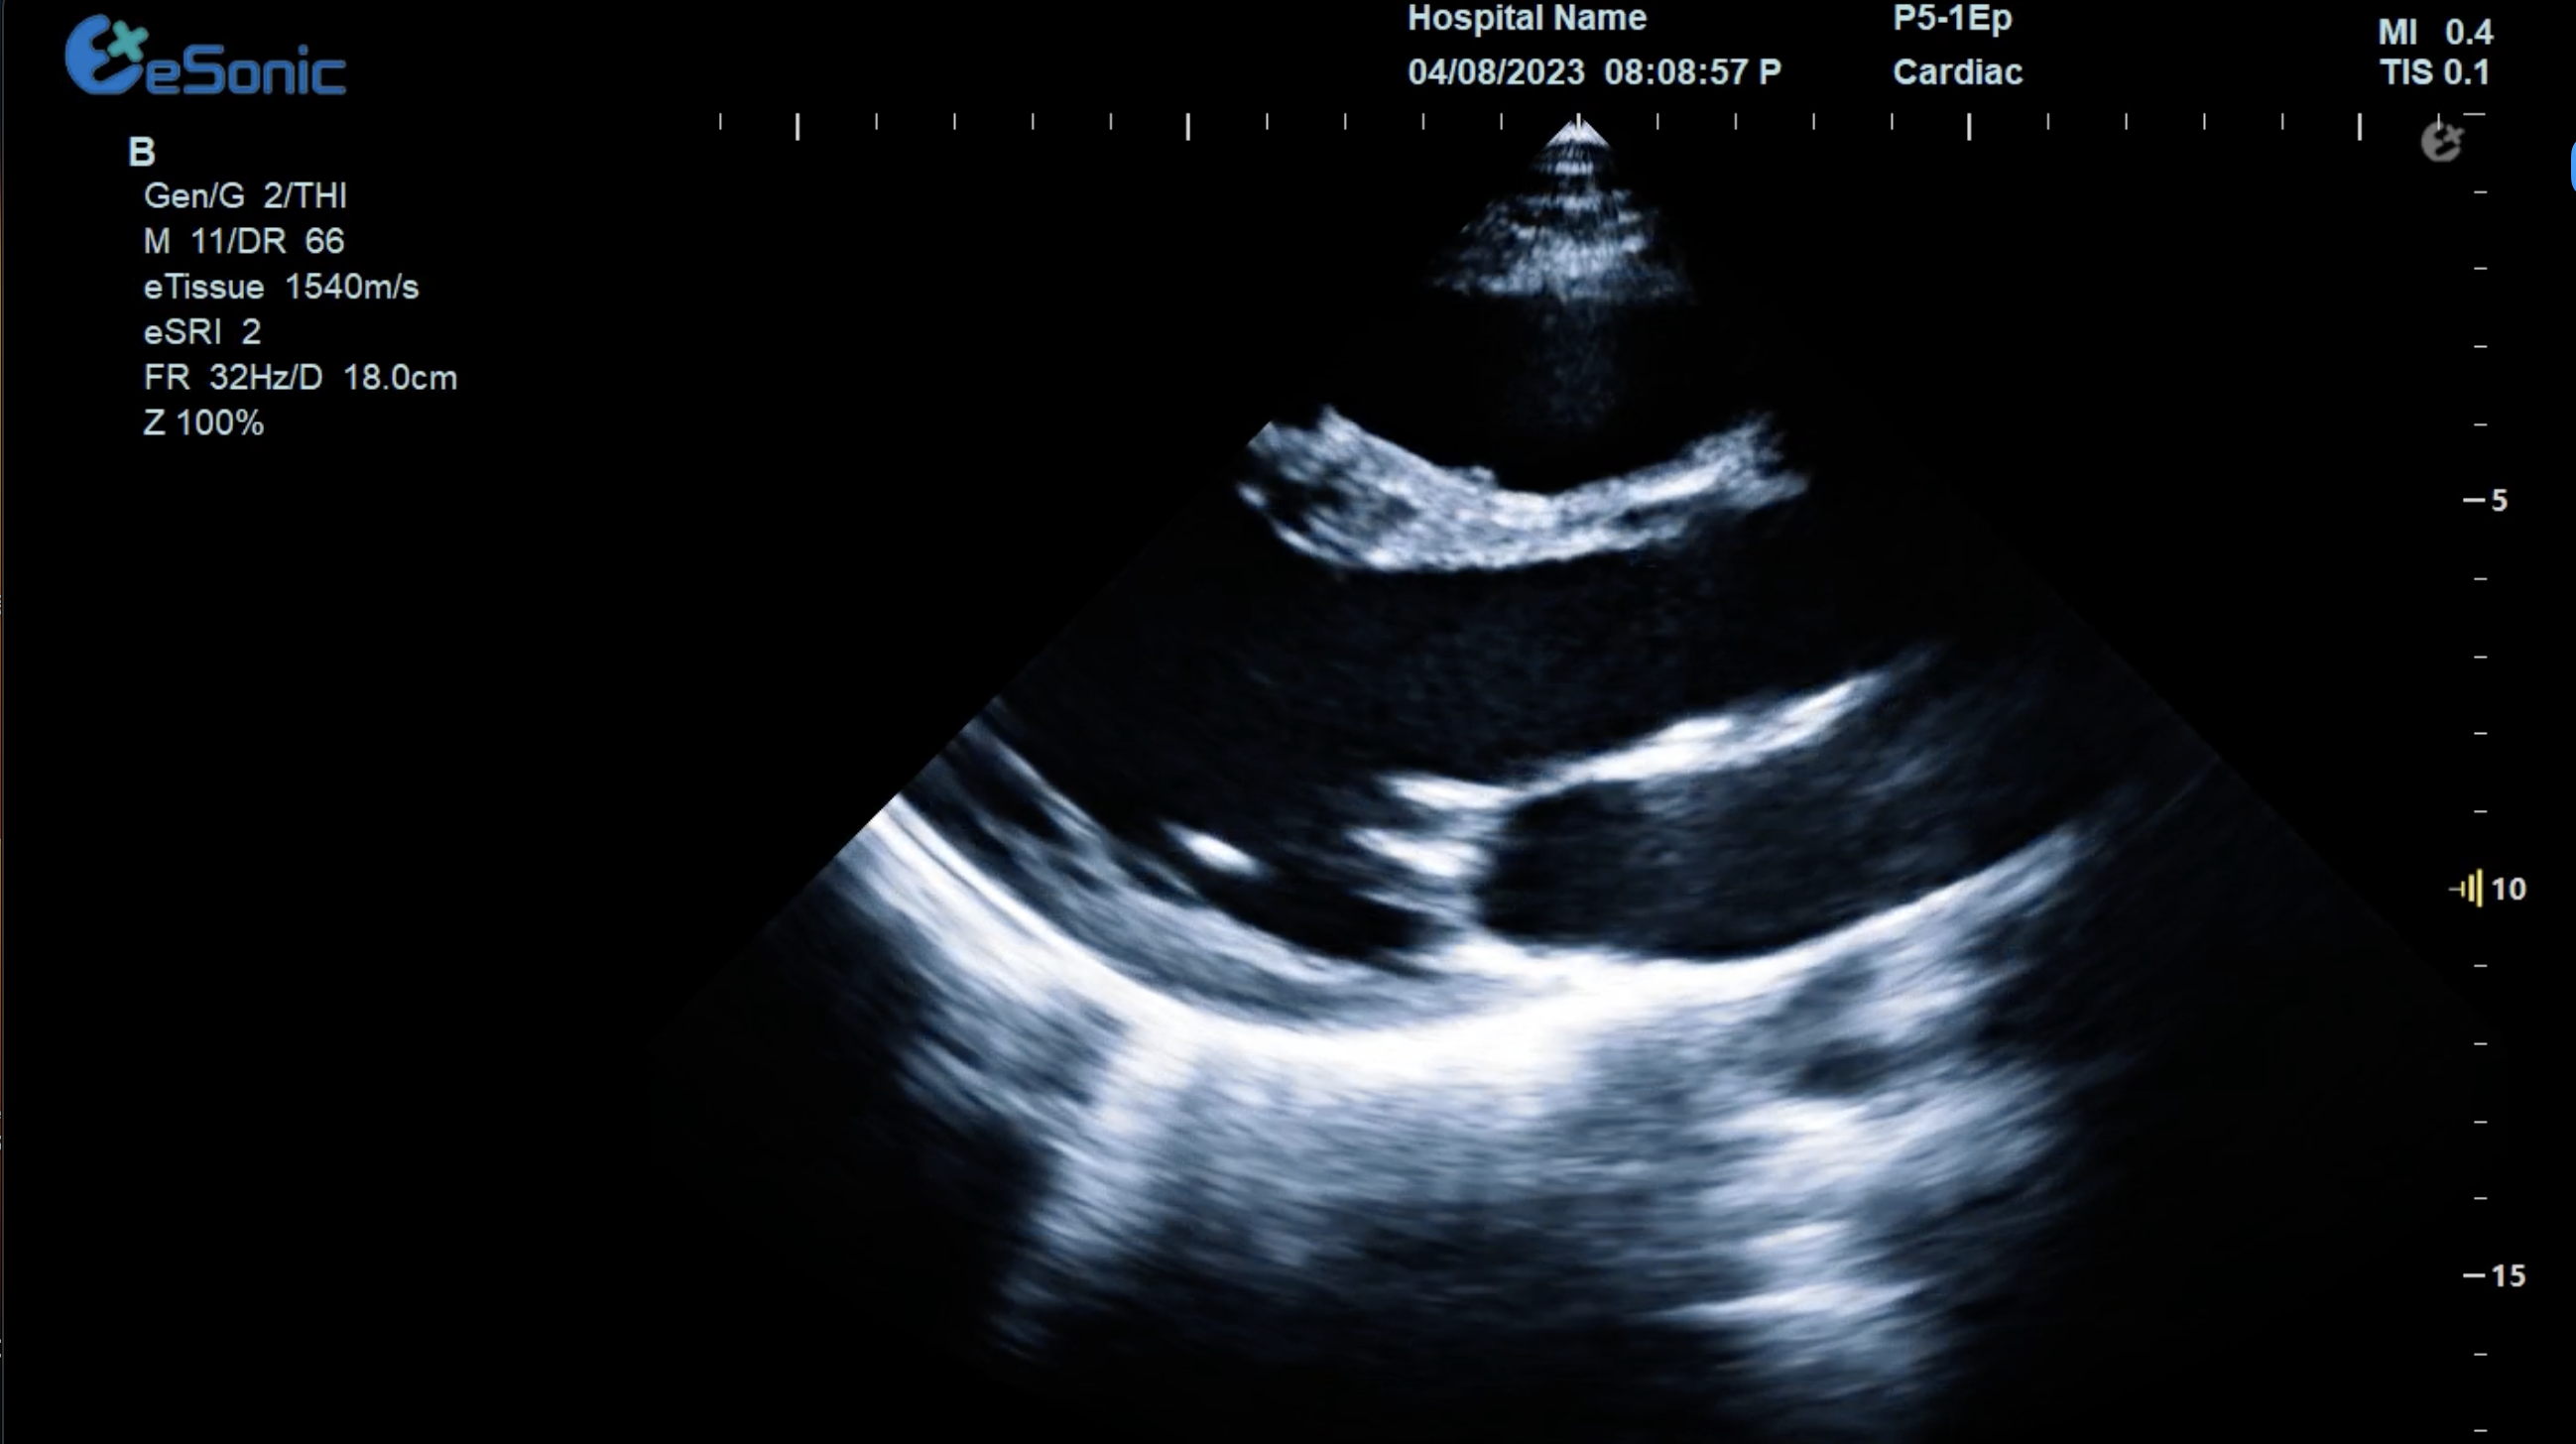

胸骨旁左心室长轴切面image.png

扫查方法:探头放在胸骨左缘三到四肋间或距胸骨2-3cm处,探头标记指向患者右肩大约9-10点位置

超声声像图:显示左房、左室、主动脉、右室、室间隔及后壁;同时,此切面可观察二尖瓣及主动脉瓣的形态及运动。